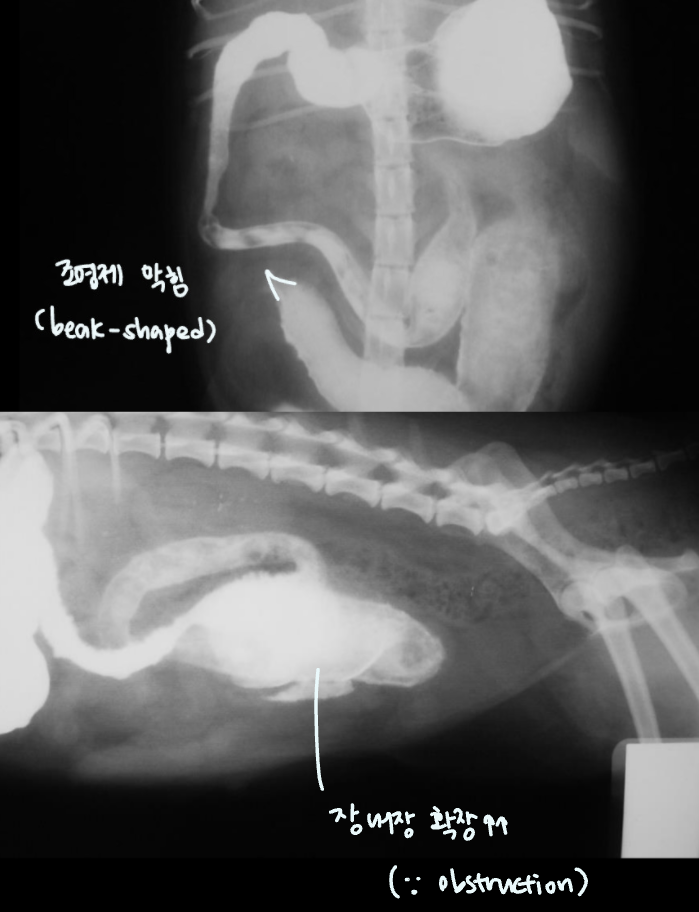

| Beak-shaped intestinal obstruction | DDx) |

| ๋์ฌ์์์ ์ฆ์์ด ๋ํ๋ ์ฅ๋ฒฝ์ด 360๋๋ก ๋นํ๋๋ฉด์ ์ ์ฒด์ ์ผ๋ก ์ข์์ง โ ์กฐ์์ ์ ์ฃผํ์ด ๋๊ฒจ ๋ถ๋ฆฌ์ฒ๋ผ ๋ํ๋๋ ๋ชจ์ ![]() ![]() | Intestinal mass 1. lymphoma 2. MCT |